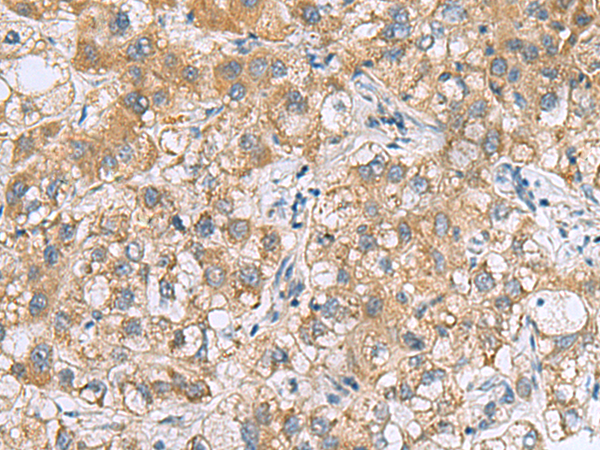

分类: 科研抗体货号: P10690别名: TIM; KIM1; TIM1; CD365; HAVCR; KIM-1; TIM-1; TIMD1; TIMD-1; HAVCR-1应用: WB,IHC反应种属: Human